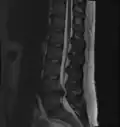

L'imagerie par résonance magnétique peut montrer la hernie, le canal vertébral, les nerfs, les tissus environnants. Les tissus mous sont les mieux analysés par cet examen qui est le plus performant pour le diagnostic de hernie discale. Les images pondérées en T2 montrent clairement la hernie.

IRM cervicale sagittale montrant une hernie discale de niveau C5-C6.